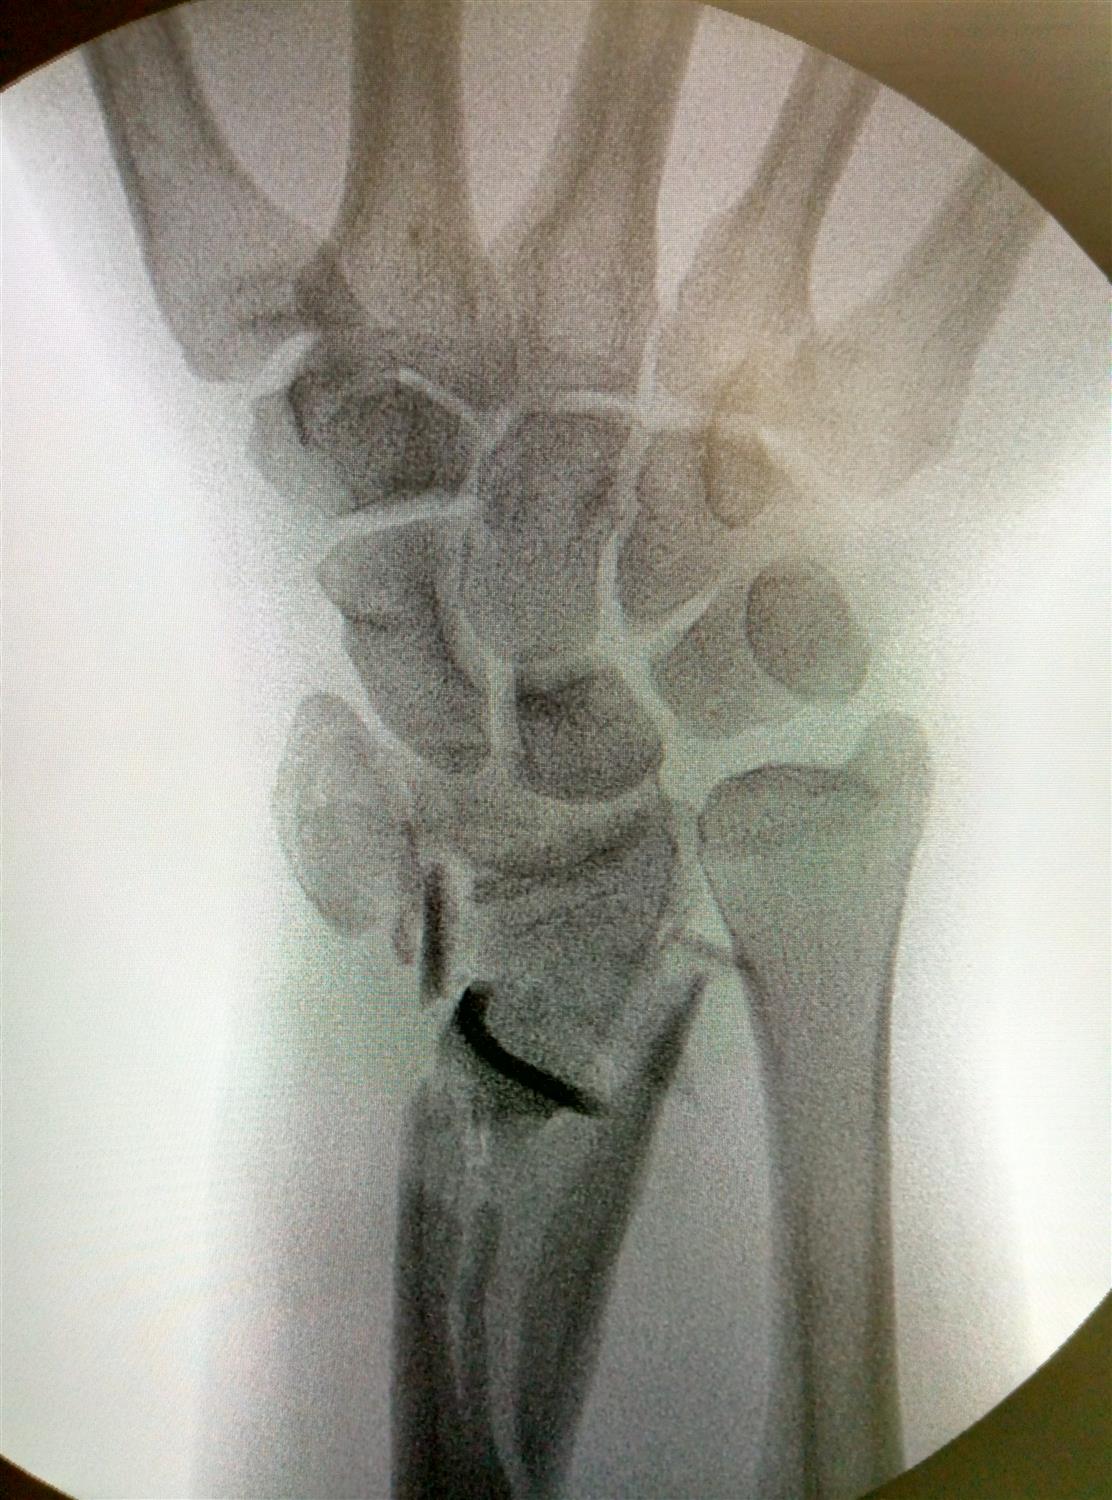

Distal Radius Ulna Fracture Orthobullets . Radial head fracture with an interosseous membrane injury extending to druj unstable relationship between ulna and radius leads to proximal migration of the radius Distal radius fractures are the most common site of pediatric forearm fractures and generally occur as a result of a fall on an outstretched hand with the wrist extended. Ulnar styloid fracture occurs together with distal radius fracture that has high degree of initial displacement associated with. Distal radius fractures are the most common orthopaedic injury and generally result from fall on an outstretched hand. The american academy of orthopaedic surgeons and the american society for surgery of the hand released updated clinical practice guidelines in. Distal radius fracture is usually associated with ulnar styloid fracture. Whether to fix the ulnar styloid or not remains a surgical dilemma as. Radius and ulnar shaft fractures, also known as adult both bone forearm fractures, are common fractures of the forearm caused by.

Radius and ulnar shaft fractures, also known as adult both bone forearm fractures, are common fractures of the forearm caused by. Whether to fix the ulnar styloid or not remains a surgical dilemma as. Distal radius fracture is usually associated with ulnar styloid fracture. Radial head fracture with an interosseous membrane injury extending to druj unstable relationship between ulna and radius leads to proximal migration of the radius Ulnar styloid fracture occurs together with distal radius fracture that has high degree of initial displacement associated with. Distal radius fractures are the most common site of pediatric forearm fractures and generally occur as a result of a fall on an outstretched hand with the wrist extended. Distal radius fractures are the most common orthopaedic injury and generally result from fall on an outstretched hand. The american academy of orthopaedic surgeons and the american society for surgery of the hand released updated clinical practice guidelines in.

Distal Radius Ulna Fracture Orthobullets Ulnar styloid fracture occurs together with distal radius fracture that has high degree of initial displacement associated with. Radius and ulnar shaft fractures, also known as adult both bone forearm fractures, are common fractures of the forearm caused by. Distal radius fractures are the most common site of pediatric forearm fractures and generally occur as a result of a fall on an outstretched hand with the wrist extended. Distal radius fractures are the most common orthopaedic injury and generally result from fall on an outstretched hand. Ulnar styloid fracture occurs together with distal radius fracture that has high degree of initial displacement associated with. The american academy of orthopaedic surgeons and the american society for surgery of the hand released updated clinical practice guidelines in. Distal radius fracture is usually associated with ulnar styloid fracture. Radial head fracture with an interosseous membrane injury extending to druj unstable relationship between ulna and radius leads to proximal migration of the radius Whether to fix the ulnar styloid or not remains a surgical dilemma as.